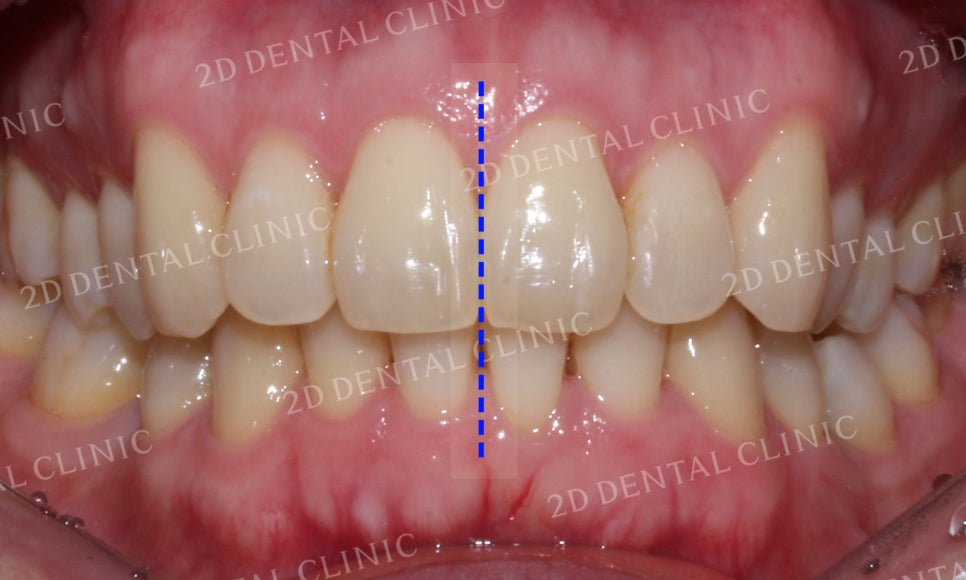

전치부을 자세히 보면

치아의 배열이 고르지 못하고

들쭉날쭉한 모습입니다.

또한 상하악 치아의 정중선이 맞지 않고

틀어져 있는 것이 확인됩니다.

전치부의 치아를 자세히 살펴보면

크라우딩으로 인해 들쭉날쭉하던 치열이

고르게 교정된 모습이고, 미세하게 틀어져 있던

상하악의 정중선 또한 잘 맞춰진 모습입니다.

교정되면서 교정 전 발견되었던

블랙트라이앵글이 악화될 수 있으니

교정치료 후 심미보철치료를 통해

치아를 수복하는 것이 좋습니다.